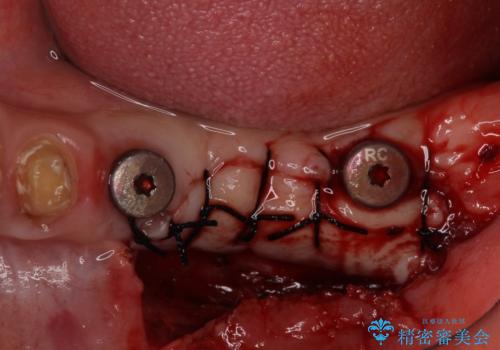

左右ともに歯根が破折しており、抜歯が必要であったため、抜歯後にインプラント補綴治療を行うこととしました。

左側は骨欠損が著しいことが予想されるため、骨造成術並びに歯肉移植術を併用することとしました。

歯肉縁下にまで虫歯が及んでいたため、歯冠長延長術を行い、清掃性の改善を試みます。